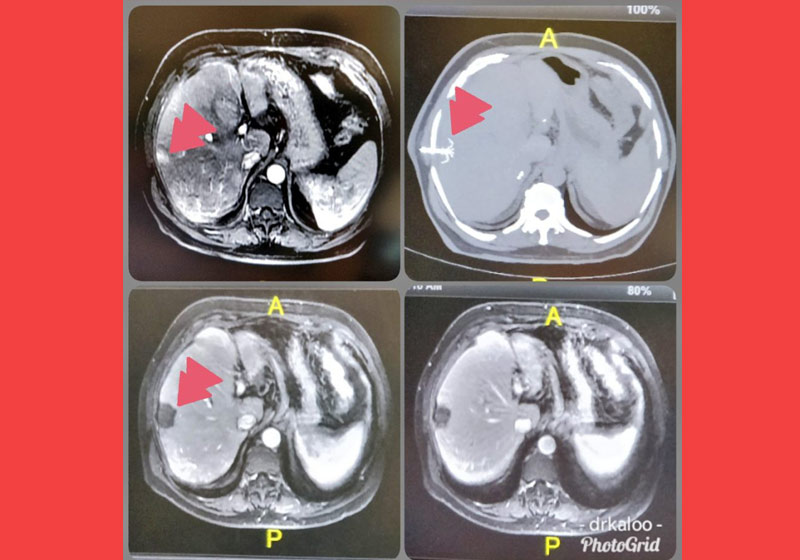

Na ablação, o médico utiliza uma agulha que é inserida no órgão afetado, até a ponta encontrar o tumor.

Para localizá-lo, são usadas imagens de ultrassom ou de tomografia.